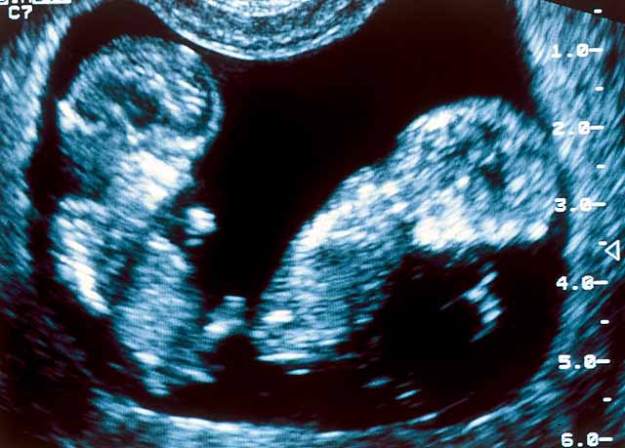

c’est l’histoire de deux fétus jumeaux dans le ventre de leur maman…